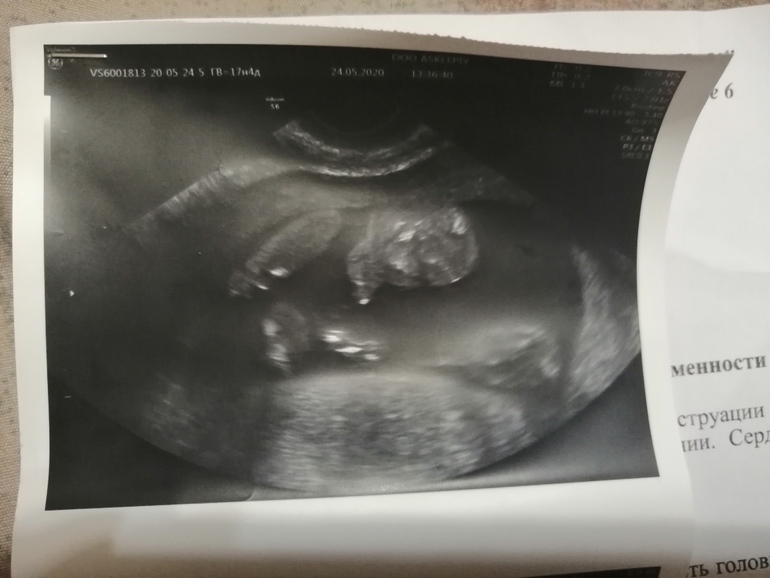

Пол малышаСделали узи на 17 неделе по животу увидел девочку, а вагинально мальчика.

Сделал фотку причиндалов.. Ну неужели это сверху такие большие яички и писюн? Кто понимает, помогите..

Я уже рассмотрела. Сверху голова, около неё рука, там прям пальчики просматривается. А снизу ноги в коленях согнутые. По ходу он мне сказал, что сделает фотку с половым и органами, а сам не сделал.

Я обвела, там прям кисть руки..

Рядом с головой. Если перевернуть фотку, то прям видно тонкие пальчики, как будто у рта, а снизу ножки, согнутые в коленях.

Извиняюсь, что мучаю вопросами.. Но просто все равно не совсем понимаю... Ножки согнуты в коленях.. И получается как будто животик и половые органы на одном уровне с коленками.. И живот для меня похож на лицо... Бредовая фотка все таки... 😀😀😀

Может я путаю снимки и тут просто малыш.. Голова и согнутые ножки.... Лицо.. Тело не видно, так как он в позе невыпрямленного тела и ножки нижняя часть... Ой с ума сойдешь.

Вот и я не понимаю... Просто он сказал, что сделает на память половые органы.. Я даже не просила.. Ну я сначала и подумала, что сверху это яички и пися.. Но сейчас смотрю и думаю.. Разве может быть такое расстояние между ногами...

Ну, я вижу на Вашем фото что-то похожее на мошонку и членик)) Но вот оно ли))

Это сынок. Тут в кадре только мошонка. Писюн сверху (в кадр не попал).Обе фотки - стоп-кадры видео, как бы вид снизу между ножек.

Ну, я вот на Вашем кадре смотрю на то, что обвела (уж извините, что стащила для редактирования - я удалю, мне чужого не надо

Просто, чтобы показать, куда смотреть), и вижу мошонку и писюн. С первого взгляда не сразу поняла. Но остальное что и где - не разберу. Да, фотка и правда чуднАя))

Теперь мне кажется, что на фото ножки, согнутые в коленях.. Затем дальше пустота, так как тело все же в положение полусогнутом, и голова лицом вперёд... А половых органов нет... Может он вообще не сделал то фото, а я ищу половые органы...

Наверно все же на этой фотке просто малыш.. Голова и ножки, и ручка около головы...